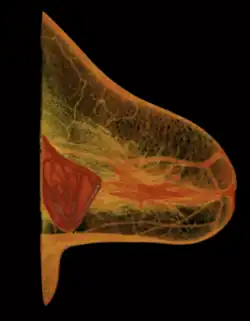

A breast implant failure: the parts of a surgically explanted breast implant are the red, fibrous capsule (left), the ruptured silicone implant (center), and the transparent filler-gel that leaked with the capsule (right).

When a silicone breast implant ruptures it usually does not deflate, yet the filler gel does leak from it, which can migrate to the implant pocket; therefore, an intracapsular rupture (in-capsule leak) can become an extracapsular rupture (out-of-capsule leak), and each occurrence is resolved by explantation. Although the leaked silicone filler-gel can migrate from the chest tissues to elsewhere in the woman's body, most clinical complications are limited to the breast and armpit areas, usually manifested as granulomas (inflammatory nodules) and axillary lymphadenopathy (enlarged lymph glands in the armpit area).[48][49][50]